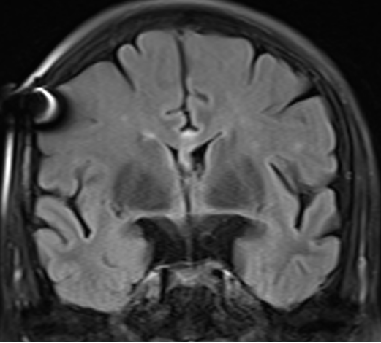

2013-8-2 MRI

2013-8-2 CT

腰穿脑压240